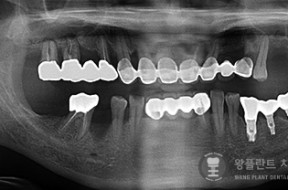

전후사례